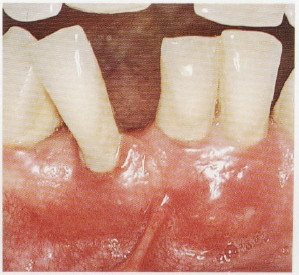

牙周炎是累及四种牙周支持组织(牙龈、牙周膜、牙槽骨和牙骨质)的慢性、炎症性、破坏性疾病。牙周最重要的支持组织就是牙槽骨,就犹如大树深深扎根在土壤中一样,我们的牙齿也牢牢的附着在牙槽骨内。当牙周炎症时,牙槽骨就会被吸收破坏,造成牙齿的“水土流失”,最终致使牙齿松动甚至脱落。